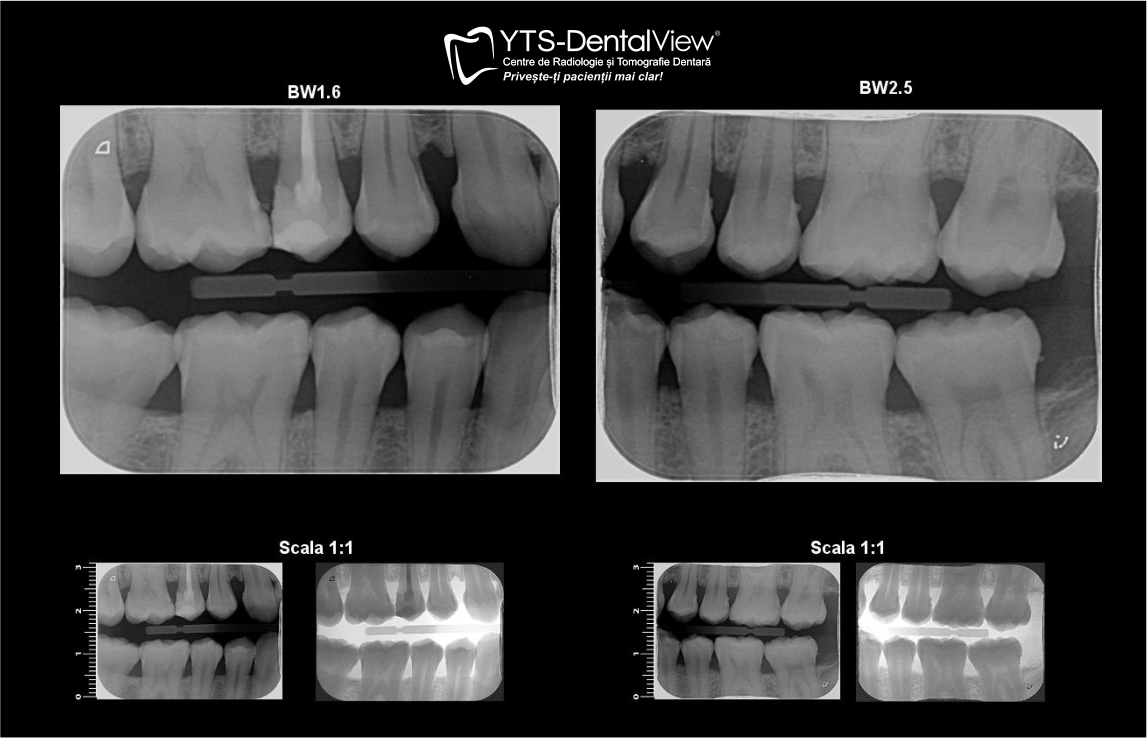

Radiografia Bitewing este un tip de radiografie dentară utilizată în stomatologia modernă, care captează o imagine amplă a coroanelor dinților superiori și inferiori. Este esențială pentru detectarea problemelor ascunse ce nu pot fi observate cu ochiul liber în timpul unui control de rutină, cum ar fi: cariile interdentare, cariile incipiente, boala parodontală sau anomalii la nivelul dinților și al osului alveolar.

Ce este radiografia Bitewing și de ce este importantă Radiografia Bitewing București este un tip specific de radiografie dentară care captează o imagine detaliată a coroanelor dinților superiori și inferiori, dar și a spațiilor interdentare. Aceasta permite diagnosticarea precoce a unor probleme care se dezvoltă în zone greu vizibile cu instrumentele clasice de examinare.

Ce probleme poate detecta radiografia BitewingRadiografia Bitewing oferă medicului stomatolog vizibilitate asupra unor afecțiuni care altfel ar rămâne ascunse:

- Cariile interdentare aflate în stadii incipiente, dificil de observat în timpul unui examen vizual

- Cariile de sub obturațiile existente – zonele defectuoase care necesită reintervenție

- Evaluarea stării parodontale – gradul de pierdere osoasă în zonele posterioare

- Monitorizarea stării dinților posteriori în timpul tratamentelor sau înainte de proceduri chirurgicale

Cum se realizează radiografia Bitewing la YTS Dental ViewLa YTS Dental View, procedura de radiografie Bitewing București se face cu ajutorul echipamentelor digitale de ultimă generație, inclusiv tehnologia Vista Scan, care asigură imagini clare și detaliate.